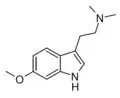

| Chemical structure | Short Name | Origin | Ring Substitution | RN1 | RN2 | Full Name | CAS Number |

|---|---|---|---|---|---|---|---|

| 5-MeO-DMT | Animals, plants | 5-OCH3 | CH3 | CH3 | 5-methoxy-N,N-dimethyltryptamine | 1019-45-0 |